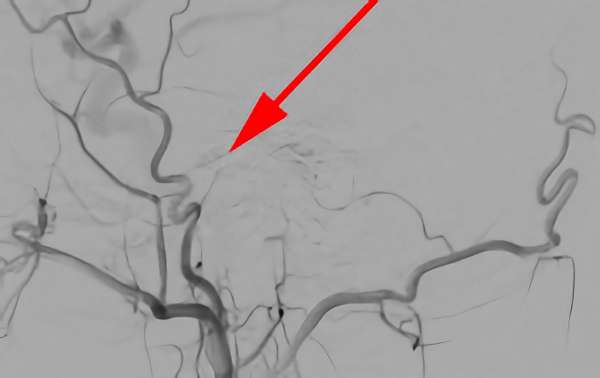

'25年4月

くも膜下出血

右内頚動脈脳動脈瘤破裂

50代

救急外来

No.1544 手術前

No.1544 手術中

No.1544 手術後